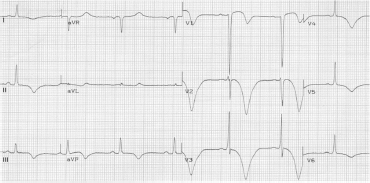

Paciente com 35 anos de idade, do sexo feminino, apresenta súbito rebaixamento do nível de consciência, associado a vômitos e a um episódio de crise convulsiva tônico clônico generalizada de dois minutos de duração. Apenas tabagista, sem outras comorbidades.

À admissão no PS, apresenta os seguintes sinais vitais: FR 12, SatO2 91% a.a., FC 56, PA 150x90 nos quatro membros. Exame neurológico: Glasgow 6, pupilas isofotorreagentes, com boa perfusão periférica. Glicemia capilar = 88mg/dL. Doente é intubada por não proteção de via aérea. Realizado o seguinte eletrocardiograma:

Após estabilização clínica, indique o exame que deve ser solicitado imediatamente para essa paciente.